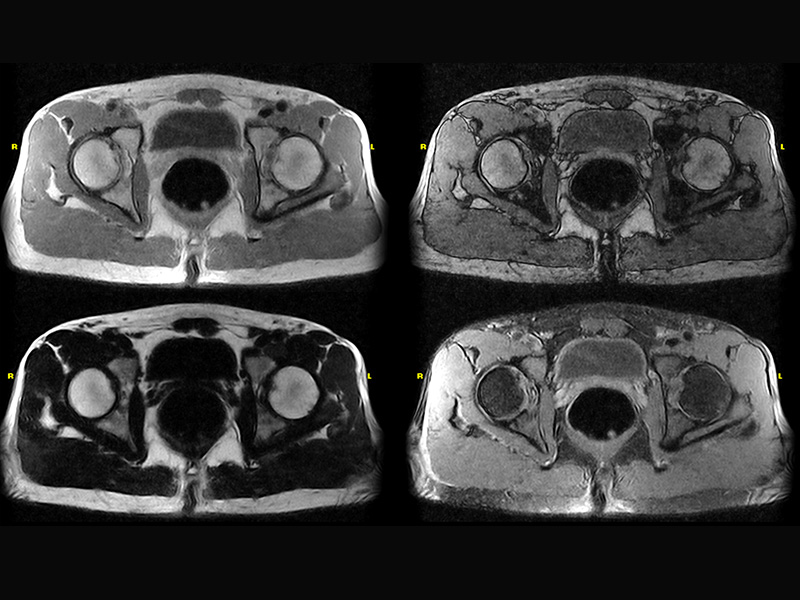

Klinické snímky